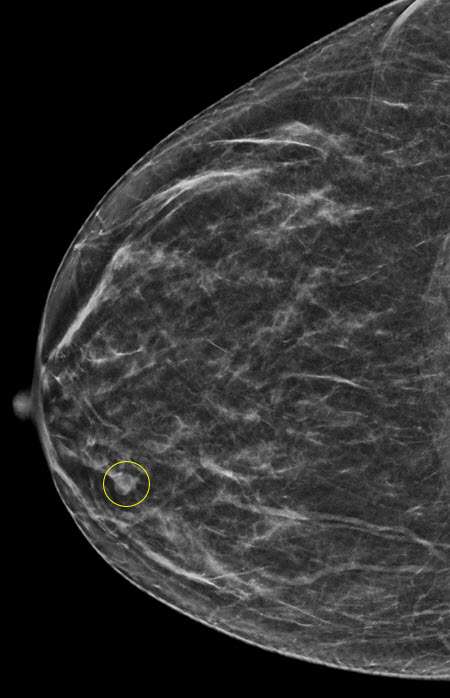

Mammographic features include:

- Intraductal papillomas may appear as well-circumscribed, round or oval opacities on often located in the subareolar region. Associated calcifications may be seen.

- In some cases, intraductal papillomas may present as only calcifications with varying morphology.